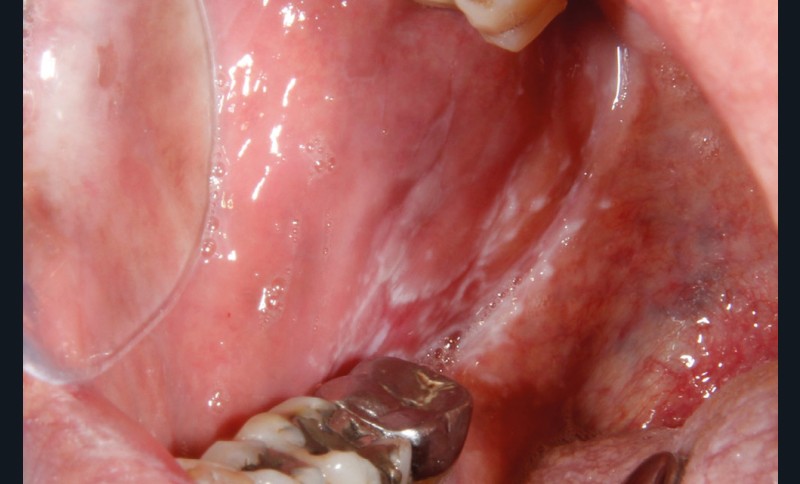

À l’interrogatoire, le patient affirme qu’il a des difficultés à maintenir une hygiène bucco-dentaire satisfaisante du fait des douleurs, et n’a pas pu consulter son chirurgien-dentiste pour son détartrage annuel en raison de la crise sanitaire en cours. L’examen clinique révèle une parodontite chronique (stade 3) généralisée et des lésions jugales (fig. 1 et 2), labiales (fig. 3) et gingivales (fig. 4) érythémateuses et kératosiques. Les lésions kératosiques jugales sont de type réticulé (fig. 1 et 2) ; les lésions kératosiques labiales sont associées à de petites érosions (fig. 3) ; les lésions palatines à des ulcérations (fig. 5). La langue présente une lésion blanche en « tache de bougie » (fig. 6) ; la muqueuse du plancher buccale est saine (fig. 7). Le signe de la pince est négatif. Le patient n’est pas porteur de prothèse dentaire malgré un édentement de moyenne étendue. Aucune lésion cutanée ou génitale n’est rapportée par le patient.

Le diagnostic le plus probable est le lichen plan (LP). On note, au niveau jugal, une kératinisation en réseau marquée par les stries de Wickman. Un phénomène de Koebner (exacerbation…